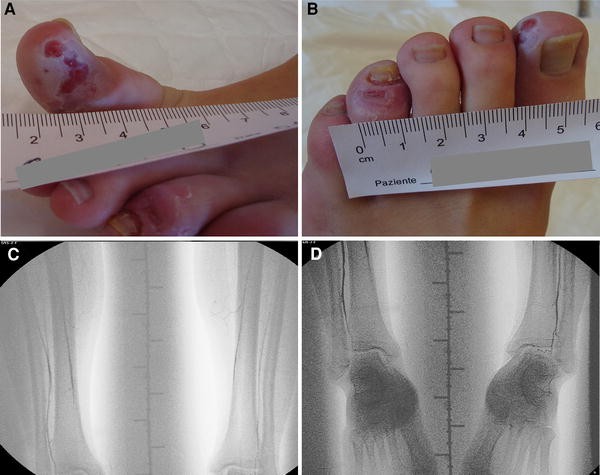

A 16-year-old female was referred to our centre because of a suspected vasculitis. From her childhood she had presented bilateral coldness and slight cyanosis of the lower extremities. In the last years, however, cyanosis and coldness progressively worsened, with the appearance of severe pain of the toes. At the same time, skin ulcers appeared on the first and fourth left toes (Fig. 1a, b).

A detailed analysis of the clinical history gave no evidence of autoimmune diseases, vasculitis or coagulation defects. Laboratory tests, such as full blood count, metabolic panel, erythrocyte sedimentation rate (ESR) and C-reactive protein (CRP) were within normal limits. Antinuclear antibodies (ANA), anti-dsDNA, anti-extractable nuclear antigens (ENA), anti-neutrophil cytoplasm antibodies (ANCA), anti-phospholipid antibodies (aPL) and lupus anticoagulant (LAC) were absent. Repeated evaluations of serum specimens, collected and separated while warm, were negative for cryoglobulins, complement fractions (C3, C4) and rheumatoid factor (RF). Other cold-related diseases were also excluded by specific tests, such as cold agglutinins or cryofibrinogen. Doppler ultrasound (US) examination of the lower extremities gave findings compatible with a complete bilateral occlusion of the posterior tibial artery with a collateral circulation maintaining a reduced blood flow below the occlusion. The US also revealed a severe bilateral stenosis of the anterior tibial artery. Complete US evaluation of the other arteries and an echocardiogram were normal. The 18F-fluorodeoxyglucose positron emission tomography (PET) did not document local metabolic activity nor gave evidence of systemic underlying disease. Magnetic resonance angiography (MRA) showed progressive narrowing of the tibial artery and its apparent absence in the distal tract, but was early interrupted because of an adverse reaction to the contrast agent. The angiogram of the lower extremities, however, confirmed the lack of blood flow to tibial arteries (Fig. 1c, d).